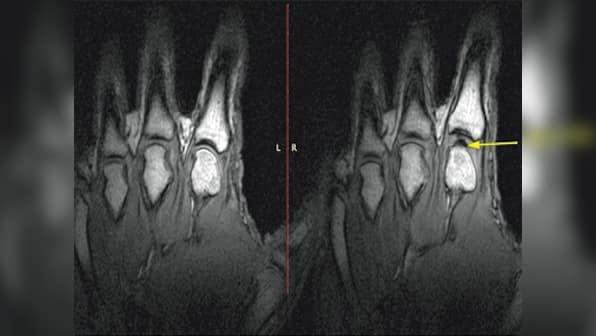

The distinctive popping sounds heard when cracking knuckles is caused due to a cavity forming rapidly inside the finger joints, scientists have found for the first time. [caption id=“attachment_2200366” align=“alignleft” width=“380”]  A vacuum is formed in the joint when the knuckles are cracked. Image: University of Alberta[/caption] “We call it the ‘pull my finger study’ - and actually pulled on someone’s finger and filmed what happens in the MRI. When you do that, you can actually see very clearly what is happening inside the joints,” said Greg Kawchuk, a professor at the University of Alberta. “It’s a little bit like forming a vacuum,” added Kawchuk, according to University of Alberta statement. “As the joint surfaces suddenly separate, there is no more fluid available to fill the increasing joint volume, so a cavity is created, and that event is what’s associated with the sound.” Scientists have debated the cause of joint cracking for decades, dating back to 1947 when UK researchers first theorised vapour bubble formation as the cause. That was put in doubt in the 1970s when another team of scientists instead fingered collapsing bubbles as the cause. The idea for the project was born when Nanaimo chiropractor Jerome Fryer approached Kawchuk about a new knuckle-cracking theory. They decided to skip the theories and with the University of Alberta colleagues, decided to actually look inside the joint. But to find an answer, the team needed someone capable of cracking knuckles on demand - a job that fell to Fryer himself. Kawchuk said most people have the ability to crack their knuckles, but unlike most, Fryer can do it in every finger, and after the standard recuperation time, he can do it again. Fryer’s fingers were inserted one at a time into a tube connected to a cable that was slowly pulled until the knuckle joint cracked. MRI video captured each crack in real time - occurring in less than 310 milliseconds. In every instance, the cracking and joint separation was associated with the rapid creation of a gas-filled cavity within the synovial fluid, a super-slippery substance that lubricates the joints. Scientists have calculated that the amount of force at work when you crack your knuckles has enough energy to cause damage to hard surfaces, yet research also shows that habitual knuckle cracking does not appear to cause long-term harm. Those conflicting results are something Kawchuk and his team plan to investigate next. “The ability to crack your knuckles could be related to joint health,” said Kawchuk, who believes this work could have implications for other joints in the body, including the spine, and help explain why joints become arthritic or injured. The study was published in the journal ‘Plos One’. Watch the video MRI video of the Pull My Finger study here: